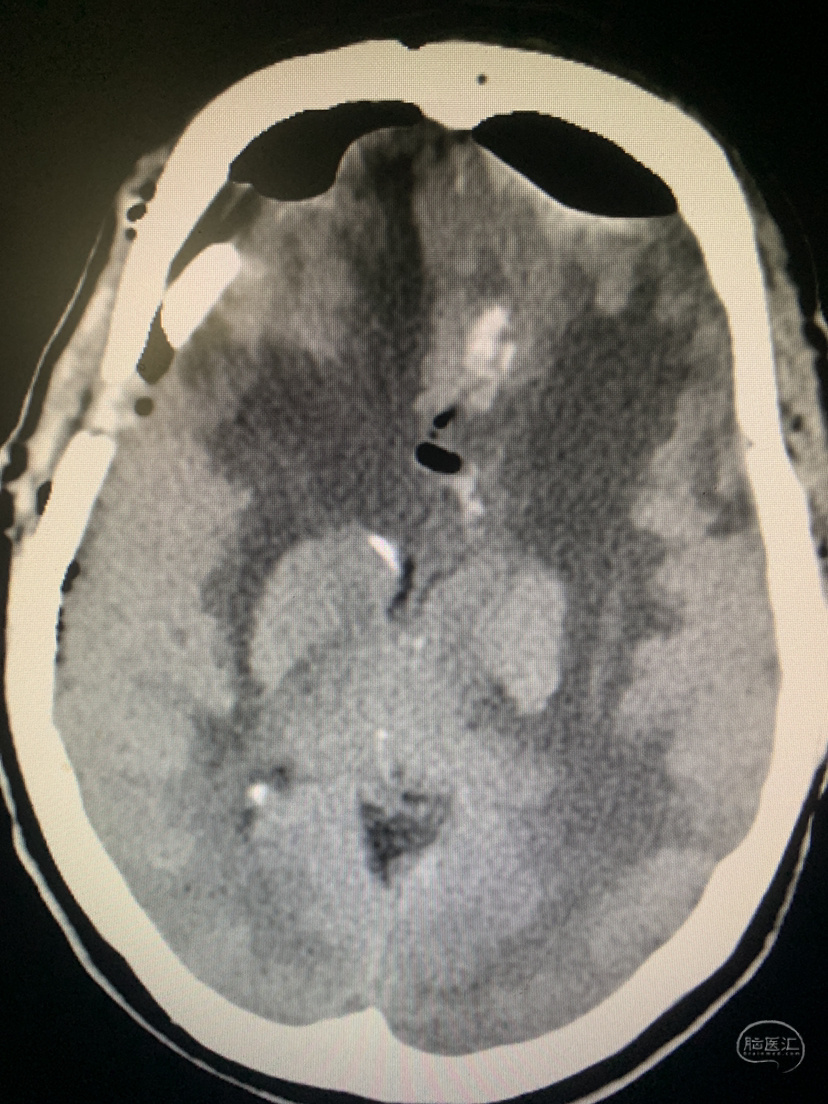

术前CT

术前CT

术后CT